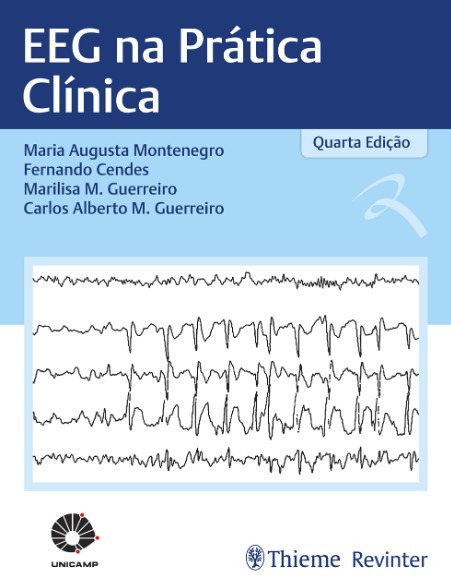

eeg 2008年 Neurovirtual / Sleepvirtual O Eletroencefalograma em Neonatosの詳細情報

Neurovirtual / Sleepvirtual O Eletroencefalograma em Neonatos。Neurovirtual / Sleepvirtual O Eletroencefalograma em Neonatos。Tênis ZX750 Bege - Adidas - Tênis Esportivo - Magazine Luiza。eeg2008年5.6.7.8.9.10.11.12月号折り目が結構あります。シャネルSUPER COLLECTION 2005 レア雑誌。⚠️古い雑誌なのでご理解の上購入お願い致します。EEG mostra foco temporal esquerdo, em montagem com Cz. | Download。9月号は写真の通りです。⚠️雑誌の状態はよくありません。スーパー戦隊 オフィシャルムック 20世紀 21世紀 42冊セット。ZOIDS ゾイド バトルコミック。